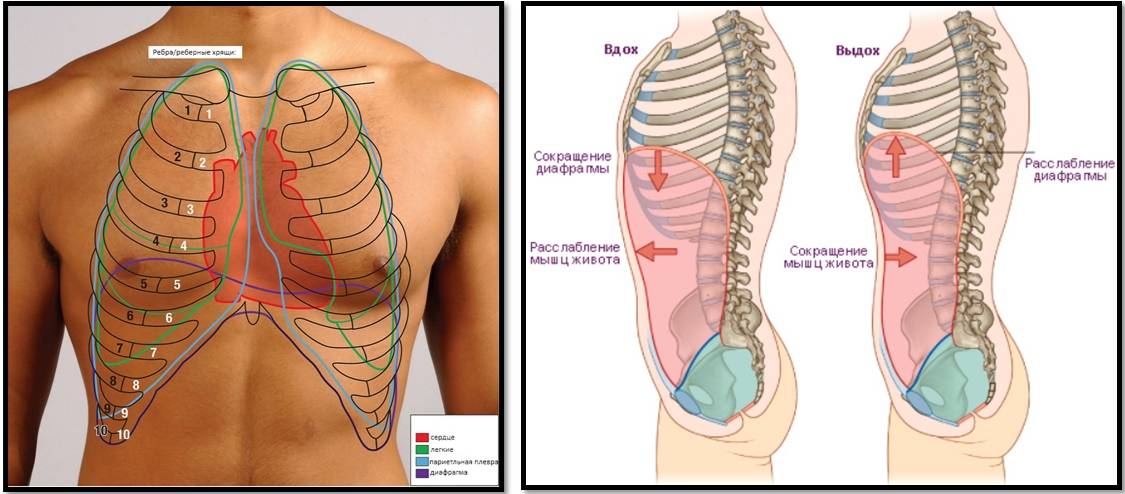

Что такое правильное дыхание

Чтобы понять, какое дыхание лучше – грудное или брюшное, следует изучить особенности движения элементов организма, которые отвечают за этот процесс. Считается, что дышать брюшным способом – лучше, чем грудным.

Чтобы понять, какое дыхание лучше – грудное или брюшное, следует изучить особенности движения элементов организма, которые отвечают за этот процесс. Считается, что дышать брюшным способом – лучше, чем грудным.

При любом типе дыхания за обработку кислорода отвечают легкие. Но их увеличение, как и изменение объема полости груди, зависит от 2 разных способов:

- При вдохе стенка груди приподнимается и отодвигается от позвоночника, из-за чего полость грудной клетки спереди увеличивается (образуется дополнительный объем между позвоночником и грудиной). В этом процессе участвуют ребра, прикрепленные к позвоночнику под острым углом. Своими концами они формируют дугу, расширяя возможный объем. Так как ребра крепятся к грудной кости, они тянут ее за собой.

- Второй способ зависит от опущения грудобрюшной преграды по направлению книзу. Это – диафрагма, имеющая куполообразную форму. Грудные мышцы отвечают в процессе дыхания за то, чтобы этот купол тянулся вниз, освобождая простор для легких. Середина опускается книзу и создается нужный объем. Из-за опущения грудная часть диафрагмы давит на живот, в результате выпячивается его стенка.

Первый тип дыхания называют грудным, а второй – брюшным. Считается, что мужчины дышат животом, а женщины – грудью. Связано это напрямую с особенностями и предназначением организма разных полов. Так как женщины во время беременности не могут полноценно дышать животом, природа предусмотрела для них другой вариант – грудной способ дыхания. У мужчин такого препятствия нет, поэтому они дышат животом.

Первый тип дыхания называют грудным, а второй – брюшным. Считается, что мужчины дышат животом, а женщины – грудью. Связано это напрямую с особенностями и предназначением организма разных полов. Так как женщины во время беременности не могут полноценно дышать животом, природа предусмотрела для них другой вариант – грудной способ дыхания. У мужчин такого препятствия нет, поэтому они дышат животом.

- Диафрагмальное (брюшное), когда в момент вдоха живот выступает вперёд, а на выдохе подтягивается по направлению к позвоночнику.

Именно диафрагмальное дыхание является правильным

Именно диафрагмальное дыхание является правильным

Главный орган в брюшном дыхании — диафрагма. Диафрагмальная мышца — это куполообразная перегородка, она отделяет грудную клетку от органов, расположенных ниже в брюшной полости. На вдохе диафрагмальная мышца идёт вниз и сжимается, заставляя брюшную стенку выдвигаться вперёд. В момент выдоха диафрагмальная мышца возвращается вверх и приобретает форму купола, выгоняя воздух из лёгких.

На вдохе диафрагма движется вниз, на выдохе — поднимается вверх

На вдохе диафрагма движется вниз, на выдохе — поднимается вверх